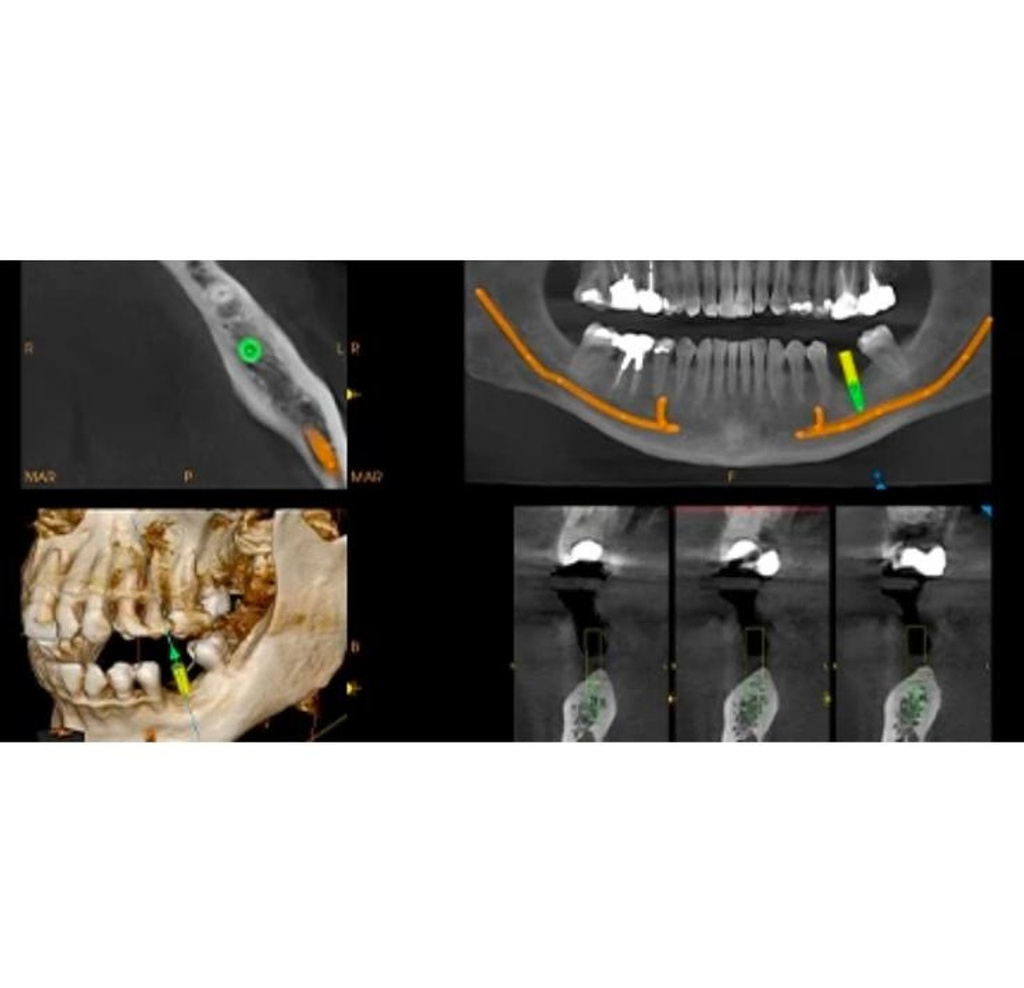

This next-gen model expands your field of view options for unparalleled flexibility. With nine selectable views ranging from 4x4 cm all the way up to 12x10 cm, the CS 8200 is equipped to cover virtually any diagnostic need your practice requires.

The CS 8200 3D blends 2D panoramic technology, CBCT imaging and 3D model scanning to create one powerful unit.

The CS 8200 3D offers multiple fields of view, to support all of your diagnostic needs — from routine exams to specialized ones.

This all-in-one unit is designed to seamlessly capture stunning 2D panoramic views and medium field of view 3D cone beam scans with ease. With a wide range of medium to large field of view settings from 4x4 cm up to 12x10 cm, the CS 8200 supports an impressive variety of specialized dental applications.

Whether you need detailed bitewing analysis, full jaw visualization, or targeted higher resolution imaging, this system's adaptable field of view has you covered. And as your practice grows, simply upgrade to add cephalometric capabilities for even greater clinical flexibility.